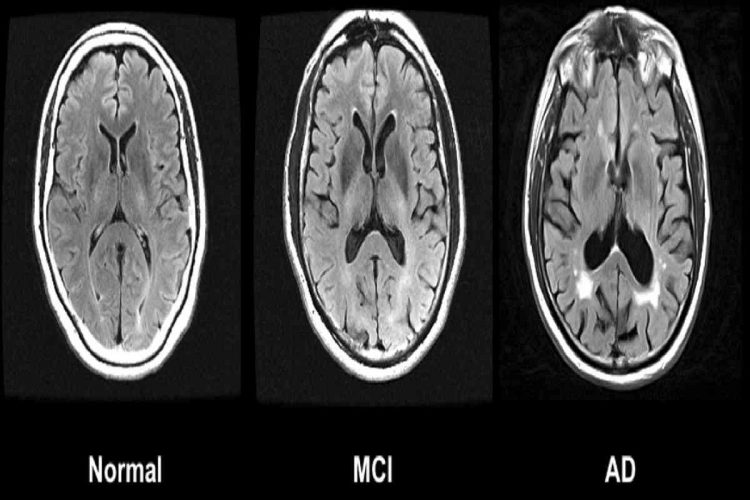

L’Alzheimer è una malattia neurodegenerativa che colpisce milioni di persone in tutto il mondo e, purtroppo, è spesso diagnosticata in fase avanzata, quando il danno cerebrale è già significativo. Le placche di beta-amiloide, una sostanza tossica che si accumula nel cervello, giocano un ruolo cruciale nello sviluppo della malattia. Il gantenerumab agisce proprio su queste placche, contribuendo a rimuoverle dal cervello e, di conseguenza, a ridurre il rischio di demenza.